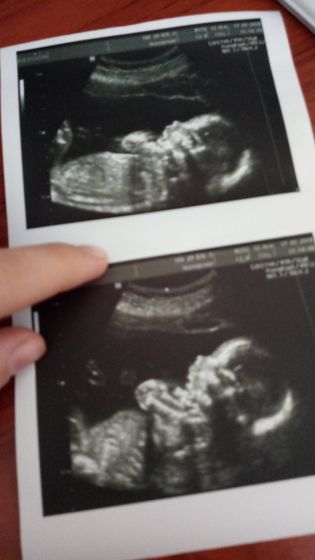

Ура, УЗИ прошли! Все у нас хорошо Ттт. Вес 312 грамм? И у нас будет мальчик ? муж ходил вместе со мной.Когда сказали пол, улыбка у него было до ушей ? Врач замечательная, все рассказала и показала, и фото на память сделала. Скоро я стану ещё мамой сыночка ?